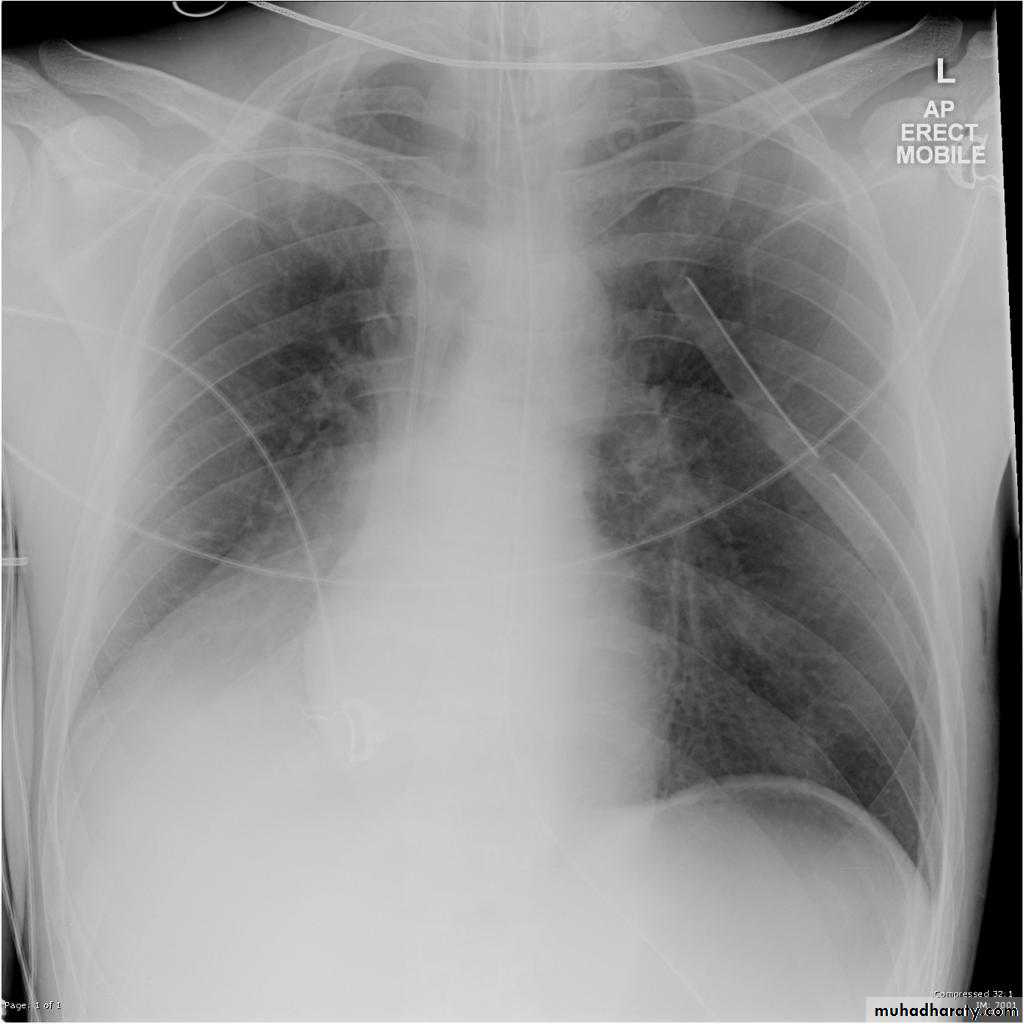

Left lower lobe collapse has distinctive features, and can be readily identified on frontal chest radiographs, provided attention is paid to the normal cardiomediastinal contours. The shadow cast by the heart does however make it harder to see than the right lower lobe collapse

Radiographic features

Left lower lobe collapseis readily identified in a well penetrated film of a patient with normal sized heart, but can be challenging in the typical patient with collapse, namely unwell patients, with portable (AP) often under-penetrated films, often with concomitant cardiomegaly. Features to be observed include :

triangular opacity in the posteromedial aspect of the left lung

edge of collapsed lung may create a 'double cardiac contour'

left hilum will be depressed

loss of the normal left hemidaphgragmatic outline

loss of the outline of the descending aorta

Non-specific signs indicating left sided atelectasis are usually also be present including:

elevation of the hemidiaphragm

crowding of the left sided ribs

shift of the mediastinum to the left

On lateral projection the left hemidiaphragmatic outline is lost posteriorly and the lower thoracic vertebrae appear denser than normal (they are usually more radiolucent than the upper vertebrae) .

Total lung collapse